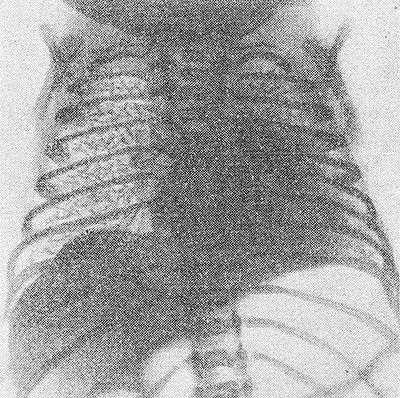

![Рис. 2. Рентгенограмма грудной клетки ребенка 15 часов жизни, страдающего гиалиново-мембранной болезнью: на всем протяжении правого легкого видна характерная сетчатость легочного рисунка, ателектазы в левом легком.]()

Рис. 2. Рентгенограмма грудной клетки ребенка 15 часов жизни, страдающего гиалиново-мембранной болезнью: на всем протяжении правого легкого видна характерная сетчатость легочного рисунка, ателектазы в левом легком.

Основной методикой исследования является рентгенография грудной клетки. Рентгенологическими признаками Г.-м, б. н. на рентгенограмме легких (рис. 2) являются: 1) характерная патологическая сетчатость легочного рисунка; иногда наблюдаются беспорядочно расположенные участки уплотнения легочной ткани (ателектазы), чередующиеся с участками просветления за счет локального вздутия легких; 2) наличие светлых полосок бронхиальных разветвлений, различимых на фоне малопрозрачного легкого; 3) в тяжелых случаях имеется диффузное понижение прозрачности легочных полей (так наз. белое легкое). Отмечается необычная форма грудной клетки — с опущенными ребрами. Иногда на рентгенограмме могут наблюдаться пневмоторакс (см.), интерстициальная и медиастинальная эмфизема (см.), возникающие в связи с разрывом бронхиол.